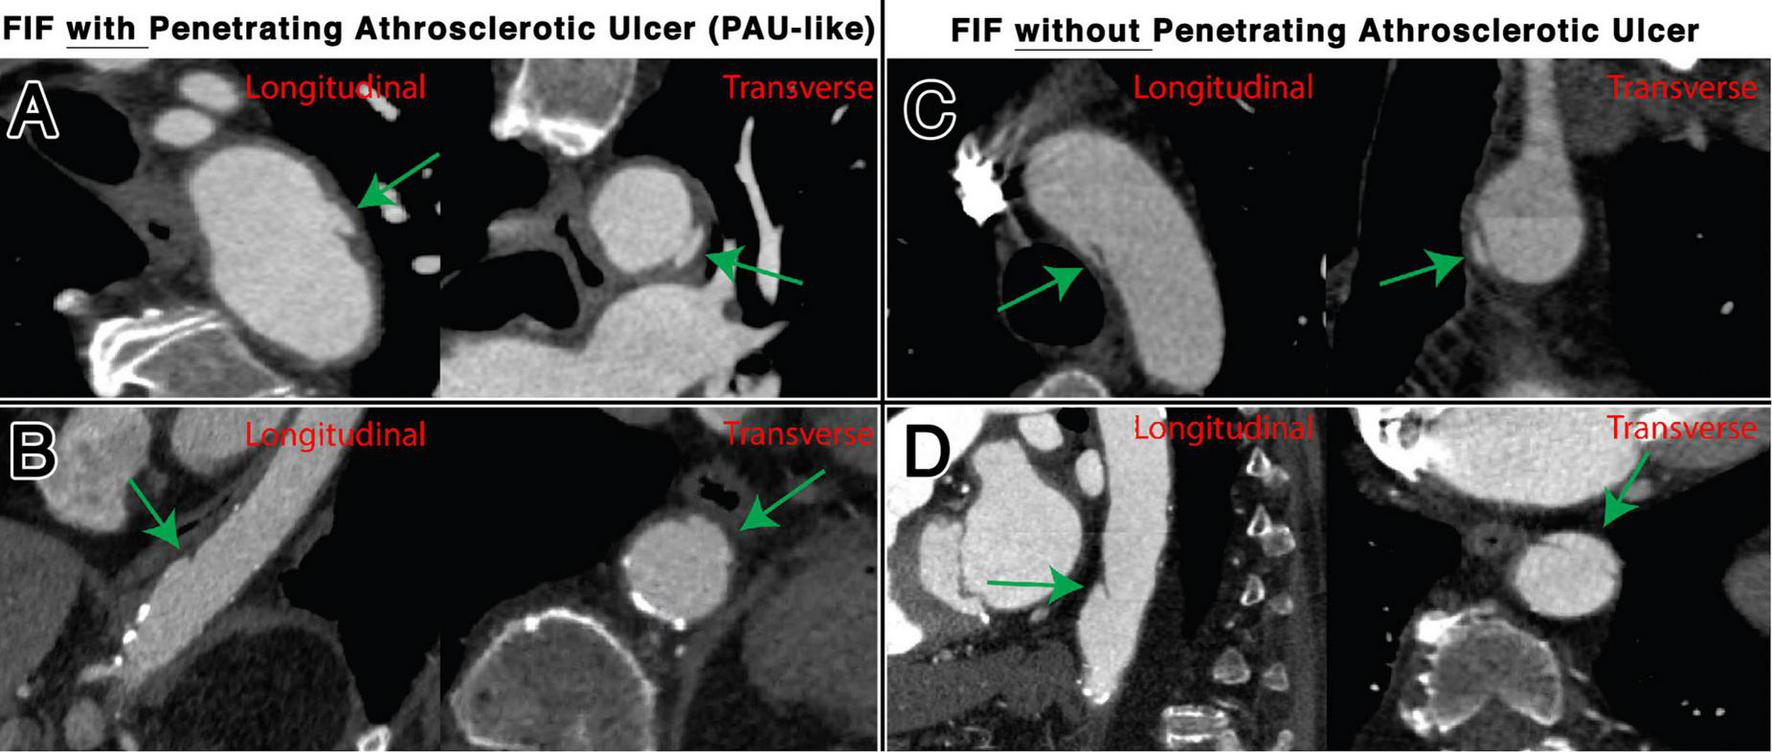

FIGURE 4

Representative examples of FIFs, with and without associated PAU, located in the thoracic aorta, shown transverse and longitudinal plane. Locations and characteristics of FIFs shown include distal aortic arch with PAU (A), distal descending thoracic aorta with PAU (B), mid arch without PAU (C), and distal descending thoracic aorta without PAU (D).